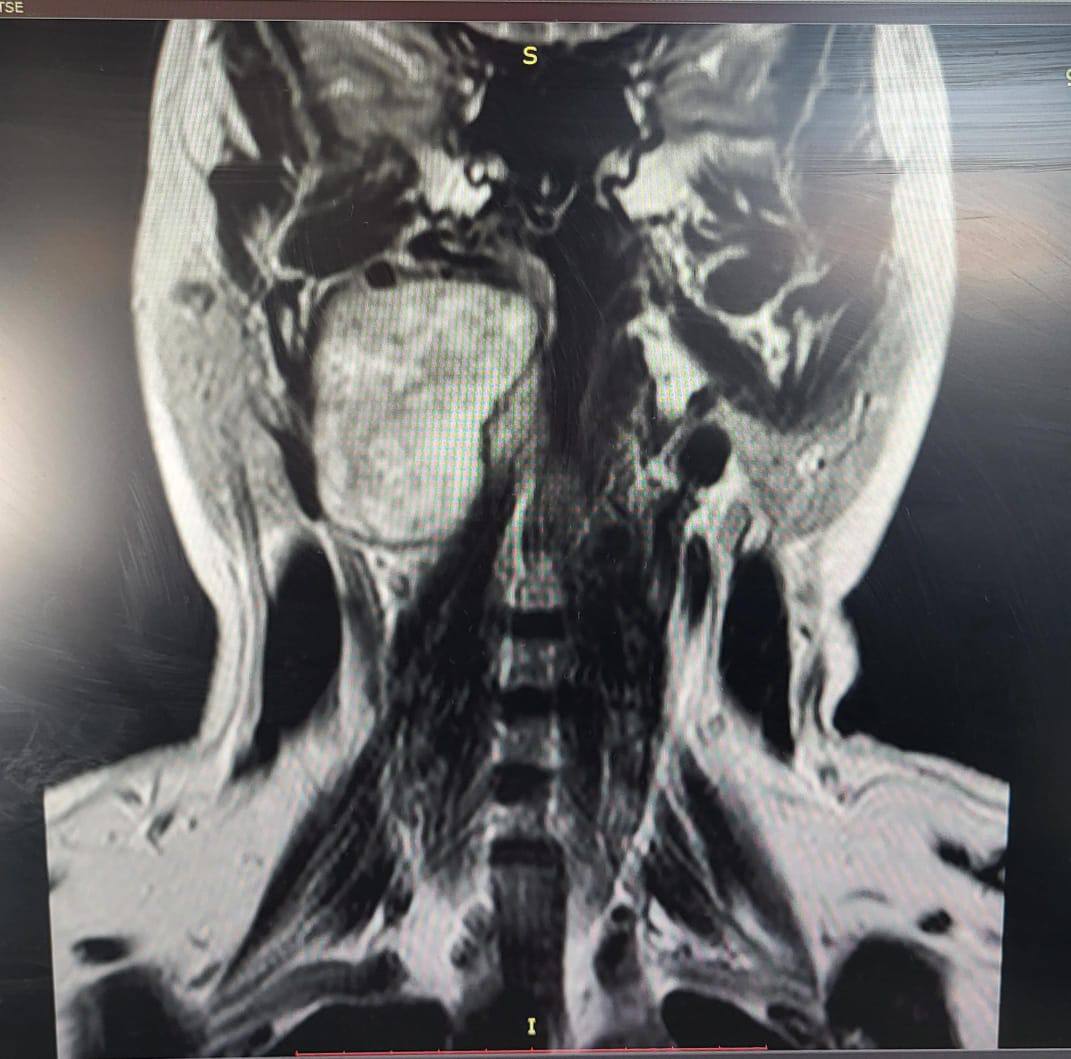

Женщина жаловалась на заложенность уха и увеличение небной миндалины. Результаты исследований выявили у нее в голове объемное образование. Это оказалась шваннома – доброкачественная опухоль, которая развивается из оболочек нервных клеток.